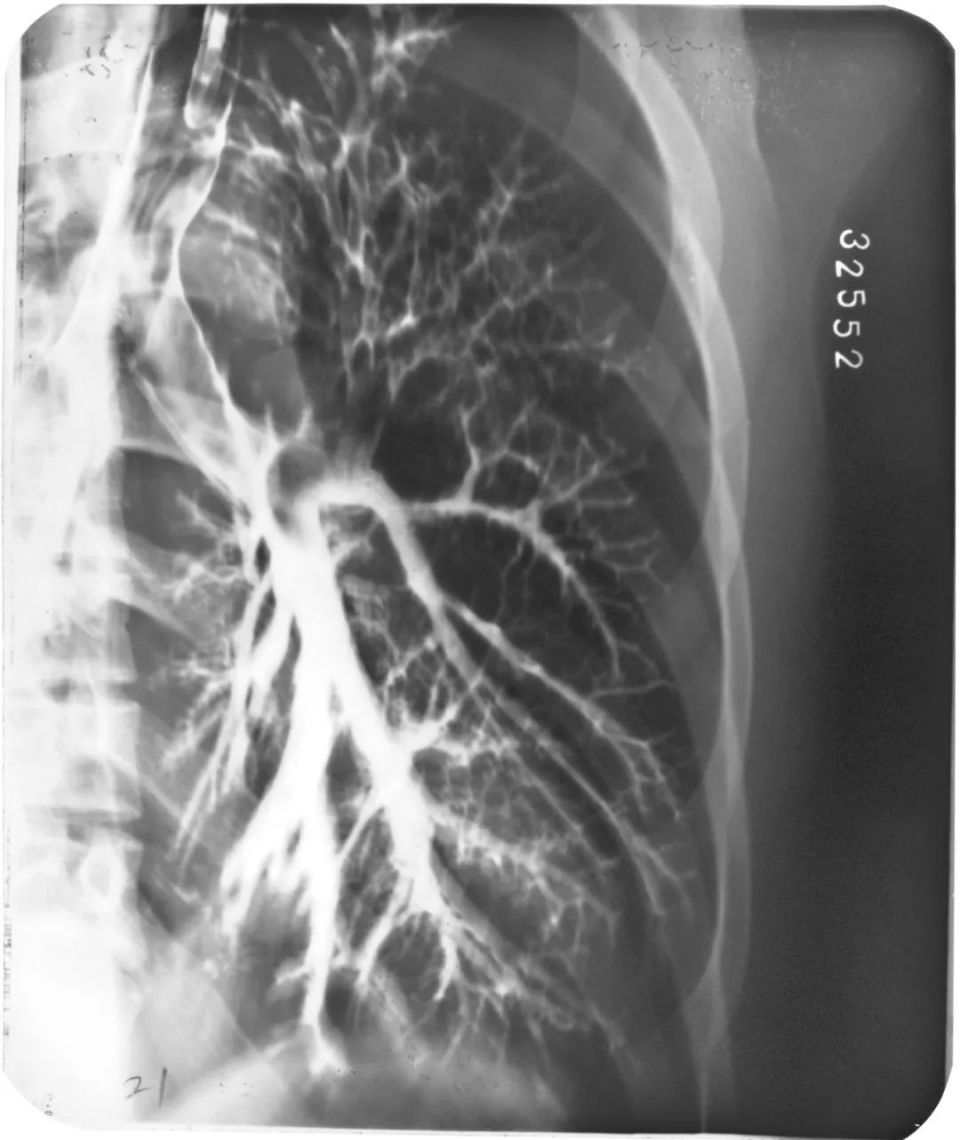

左下叶支气管扩张

图片

左下叶支气管囊状、柱状扩张

右肺支气管扩张

右肺支气管呈囊状、柱状扩张